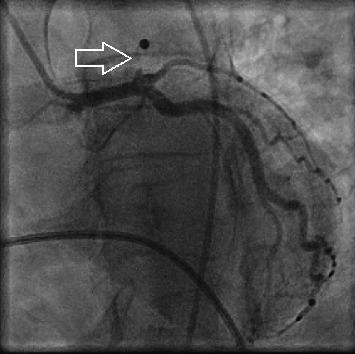

Both COVID-19 disease and cocaine consumption have prothrombotic and hypercoagulable effects and are associated with increased risk of cardiovascular events. We report the case of a patient with acute myocardial infarction in the setting of active COVID-19 disease and recent cocaine consumption. We hypothesize that COVID-19 and cocaine synergistically provoke cardiovascular events. Identifying COVID-19 disease and/or cocaine abuse as potential triggers of acute myocardial infarction can be crucial due to distinctive therapeutic consequences.

新冠病毒疾病和可卡因使用均具有促血栓形成和高凝作用,并与心血管事件风险增加相关。我们报告了一例在患有活动性新冠病毒疾病且近期使用过可卡因的情况下发生急性心肌梗死的患者。我们推测新冠病毒疾病和可卡因会协同引发心血管事件。鉴于独特的治疗后果,将新冠病毒疾病和/或可卡因滥用识别为急性心肌梗死的潜在触发因素可能至关重要。